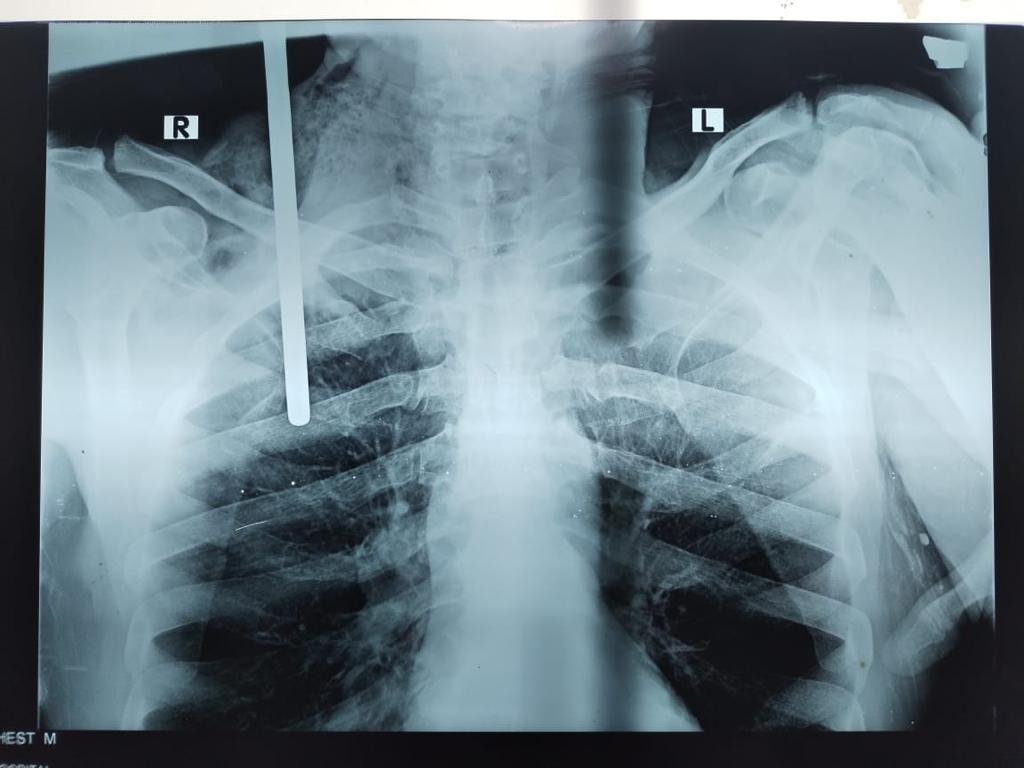

نجح فريق طبي بمستشفى الطوارىء بجامعة طنطا فى استخراج سيخ حديدي من جسم عامل اخترق جسده من جهة اليمين بين الكتف والرأس واستقر بصدره إثر سقوطه عليه أثناء تأدية عمله بإحدى شركات المقاولات.

أوضح الدكتور حسن التطاوى المدير التنفيذي لمستشفيات جامعة طنطا أن الجراحة استغرقت 5 ساعات وأن الفريق الطبى يضم كل من الدكتور محمد العيسوى المدرس بقسم جراحة الأوعية الدموية والدكتور محمد حسن عبدالعاطى المدرس المساعد بقسم جراحة الأوعية الدموية، والدكتور احمد بدوى المدرس المساعد بقسم جراحة الأوعية الدموية، والدكتور شريف طارق الطبيب المقيم بذات القسم، ومن قسم جراحة القلب والصدر الدكتور محمد الجاريه المدرس بالقسم، والدكتورة سمر محمد المدرس المساعد بذات القسم، ومن قسم التخدير الدكتورة فاطمة السماحى المدرس المساعد، والدكتور أحمد البرادعى الطبيب المقيم، وكان قد استقبل الحالة الدكتور أحمد النواجى المدرس المساعد بقسم الطوارىء.